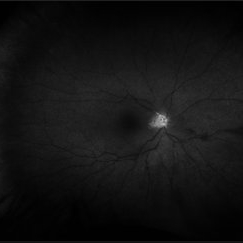

Retinitis Pigmentosa

Bilateral fundus autofluorescence images of retinitis pigmentosa.

Photographer: Olivia Rainey

Imaging device: Heidelberg Spectralis

Condition/keywords: 50 degrees, bilateral, fundus autofluorescence (FAF), hereditary retinal dystrophy, retinitis pigmentosa